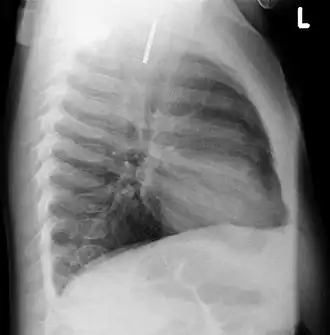

A coin seen on lateral CXR in the esophagus -

Lateral X ray showing a 9mm battery in the intestines -